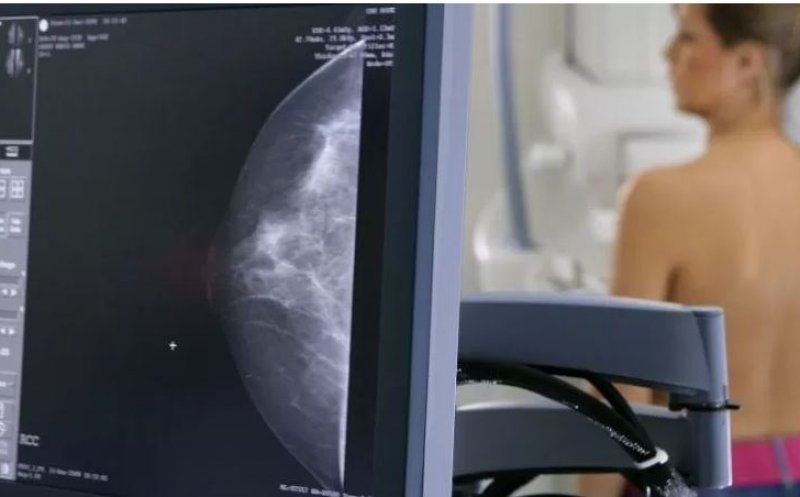

Două campanii de prevenire a cancerului de col uterin și a celui de sân vor avea loc la Cluj-Napoca în luna martie, la Cluj Arena.

Mamografiile vor fi făcute pentru femeile cu vârste cuprinse între 50 și 69 de ani.

Campania are ca obiectiv general creșterea numărului de persoane care beneficiază de programe de sănătate și de servicii orientate către prevenție, depistare precoce – screening, diagnostic și tratament precoce al cancerului de sân și se adresează femeilor cu vârsta între 50 și 69 de ani cu domiciliul/flotant în județul Cluj.